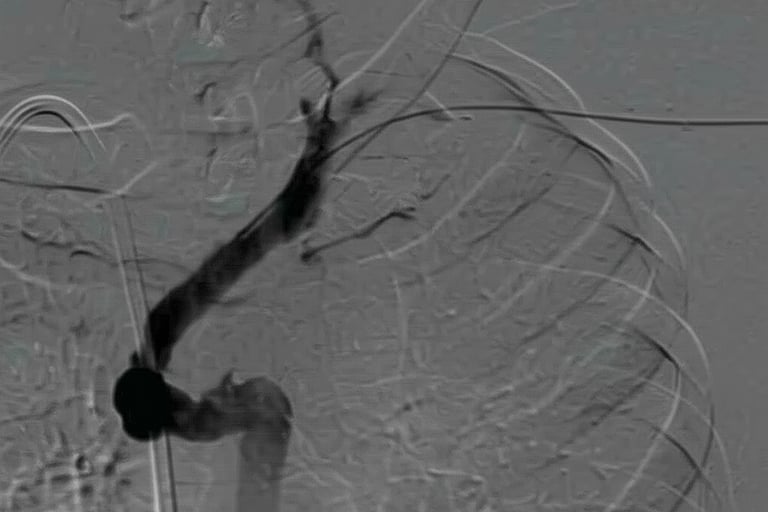

Flebografía de vena cava superior estenótica

Paso de guía Amplatz Super Stiff por zona de estenosis dentro de la vaina de fibrina